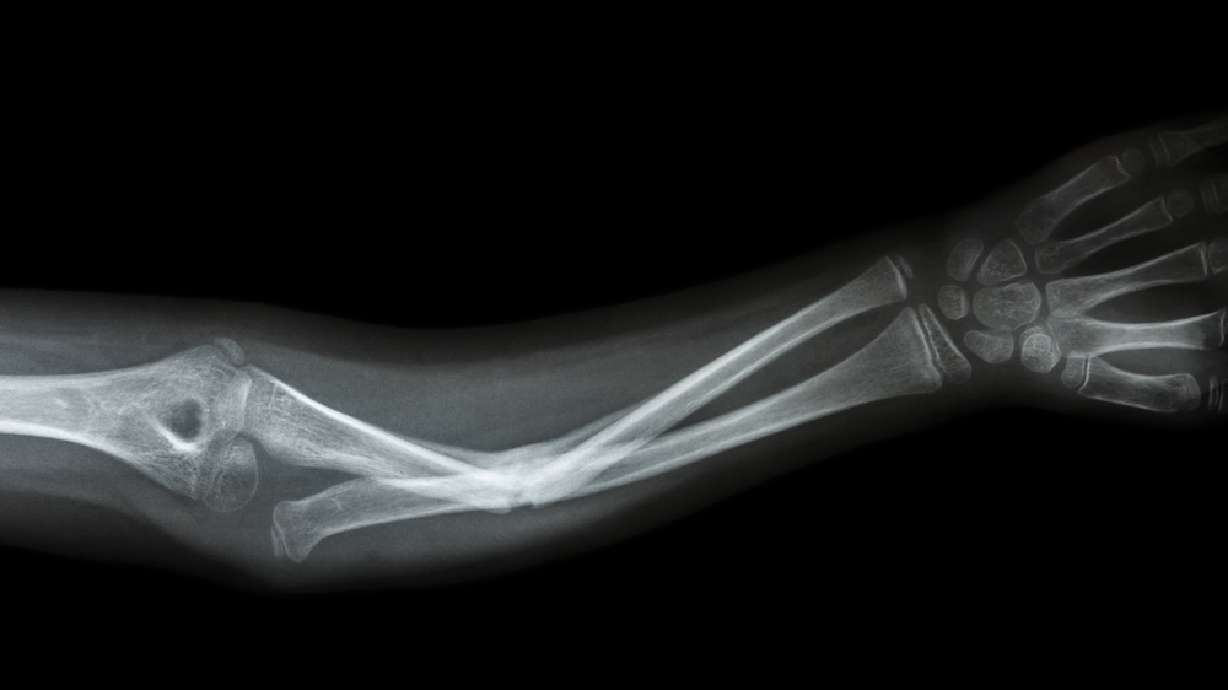

Broken arms, legs and other related injuries are another common reason for an emergency room visit. Although sports mishaps may cause basic orthopedic injuries, car accidents are the most common culprit. Winter weather results in wet and icy roads with poor visibility, and drivers are also often in a hurry. But as important as Christmas shopping or getting to your work party on time may be, it’s still more important to drive safely.